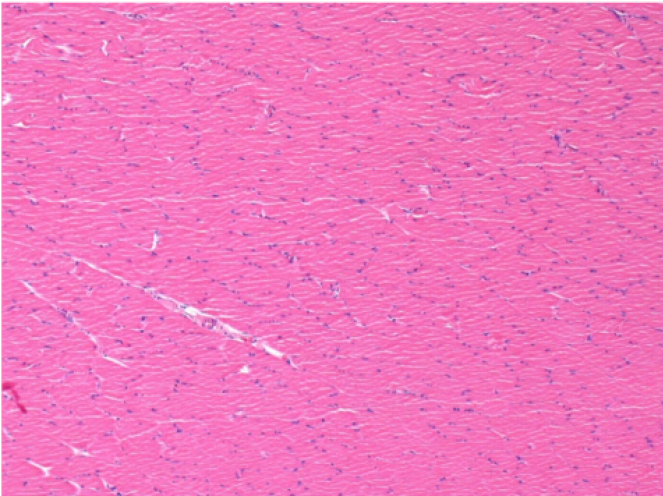

3 months (D90)after Endopeel Injection 0.1ml in the right pretibial muscle.